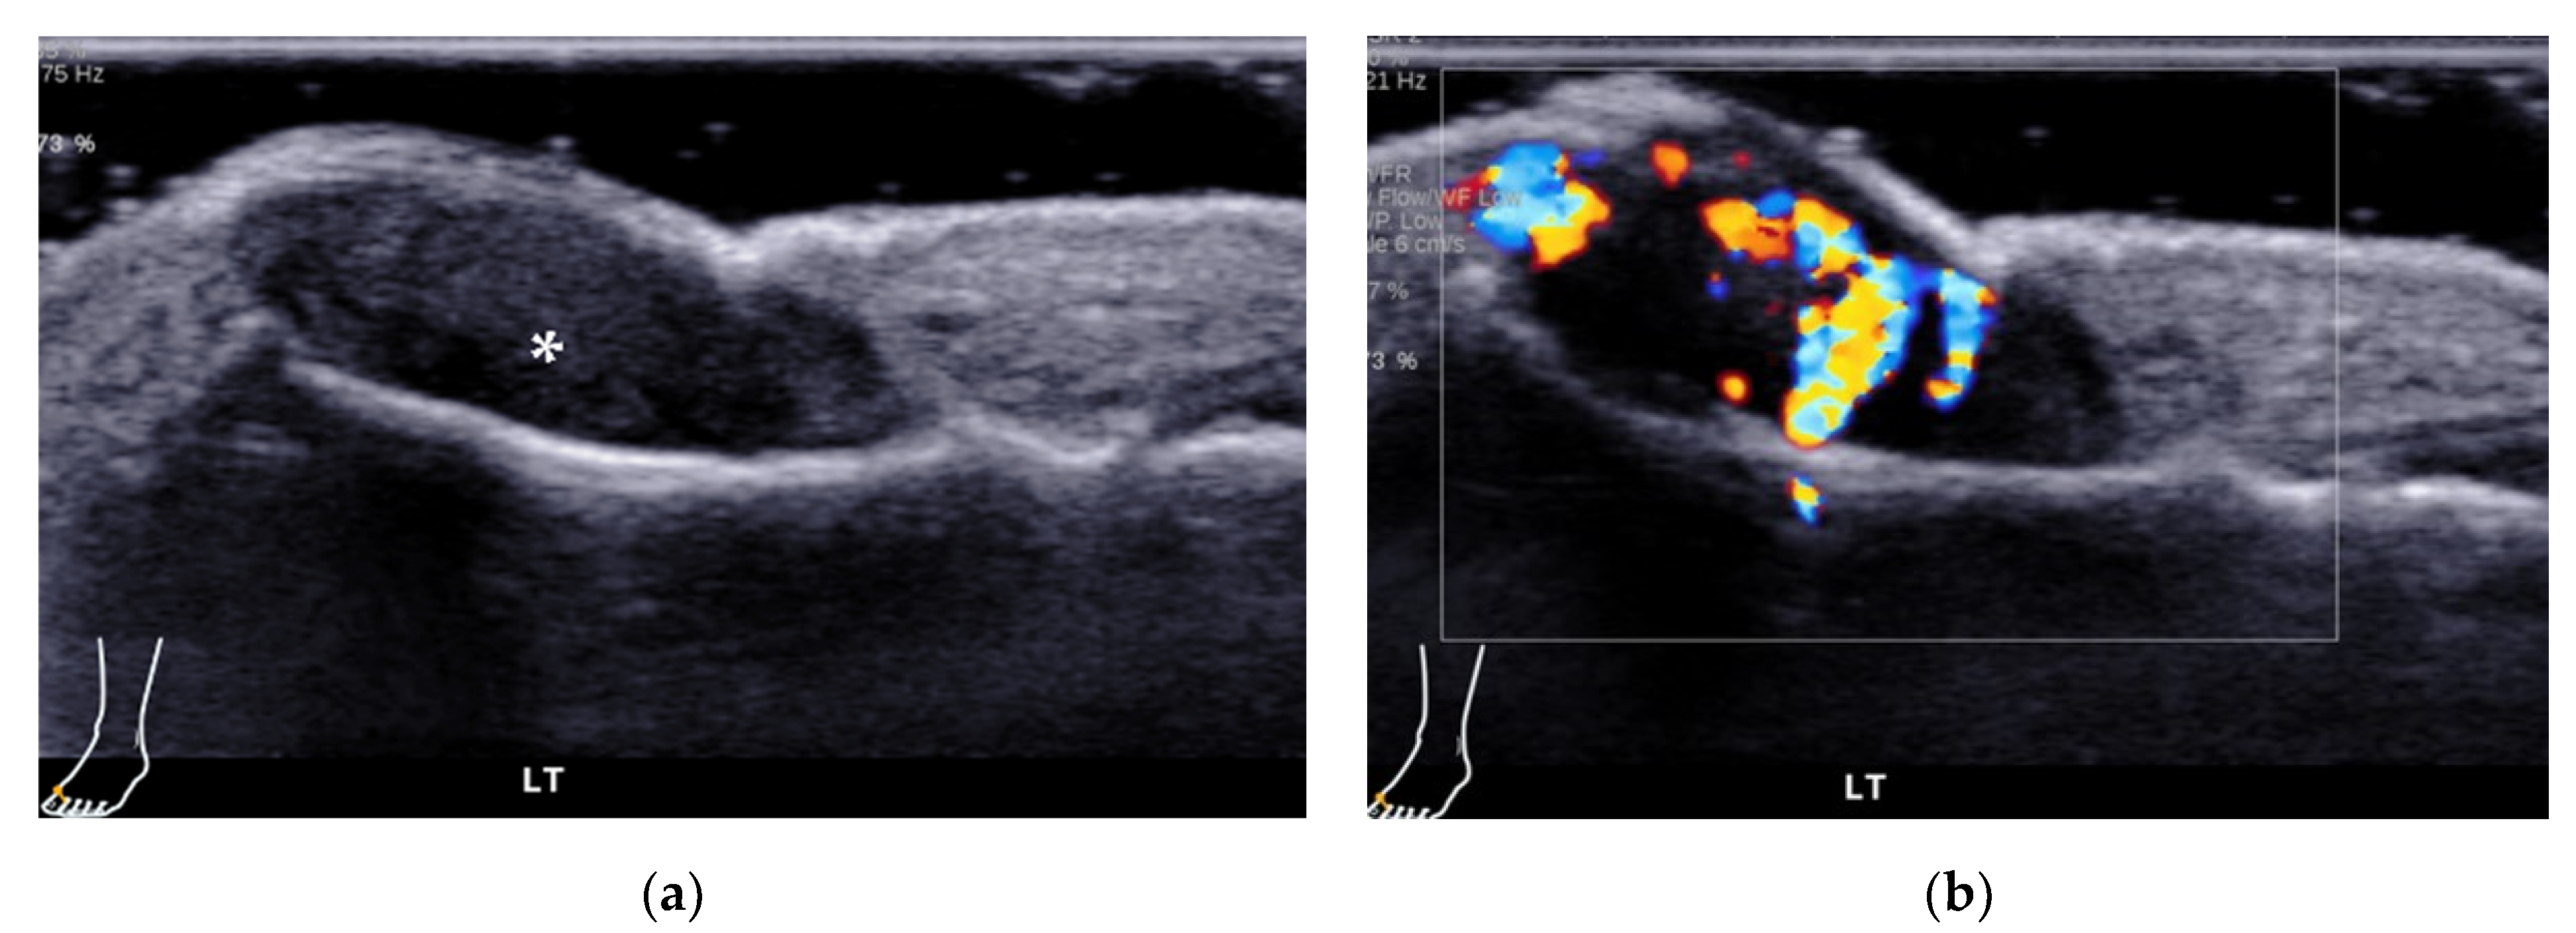

| Adventitial bursitis | plantar side of the 1st and 5th metatarsal heads | unilocular area with heterogeneous echogenicity, compressible, with or without increased vascularity |